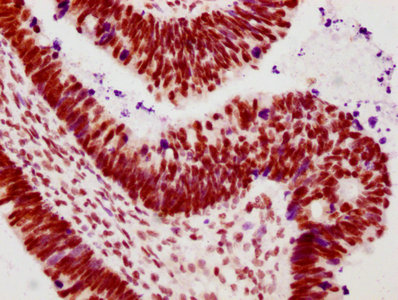

IHC image of CSB-RA018327A02phHU diluted at 1:100 and staining in paraffin-embedded human ovarian cancer performed on a Leica BondTM system. After dewaxing and hydration, antigen retrieval was mediated by high pressure in a citrate buffer (pH 6.0). Section was blocked with 10% normal goat serum 30min at RT. Then primary antibody (1% BSA) was incubated at 4℃ overnight. The primary is detected by a biotinylated secondary antibody and visualized using an HRP conjugated SP system.